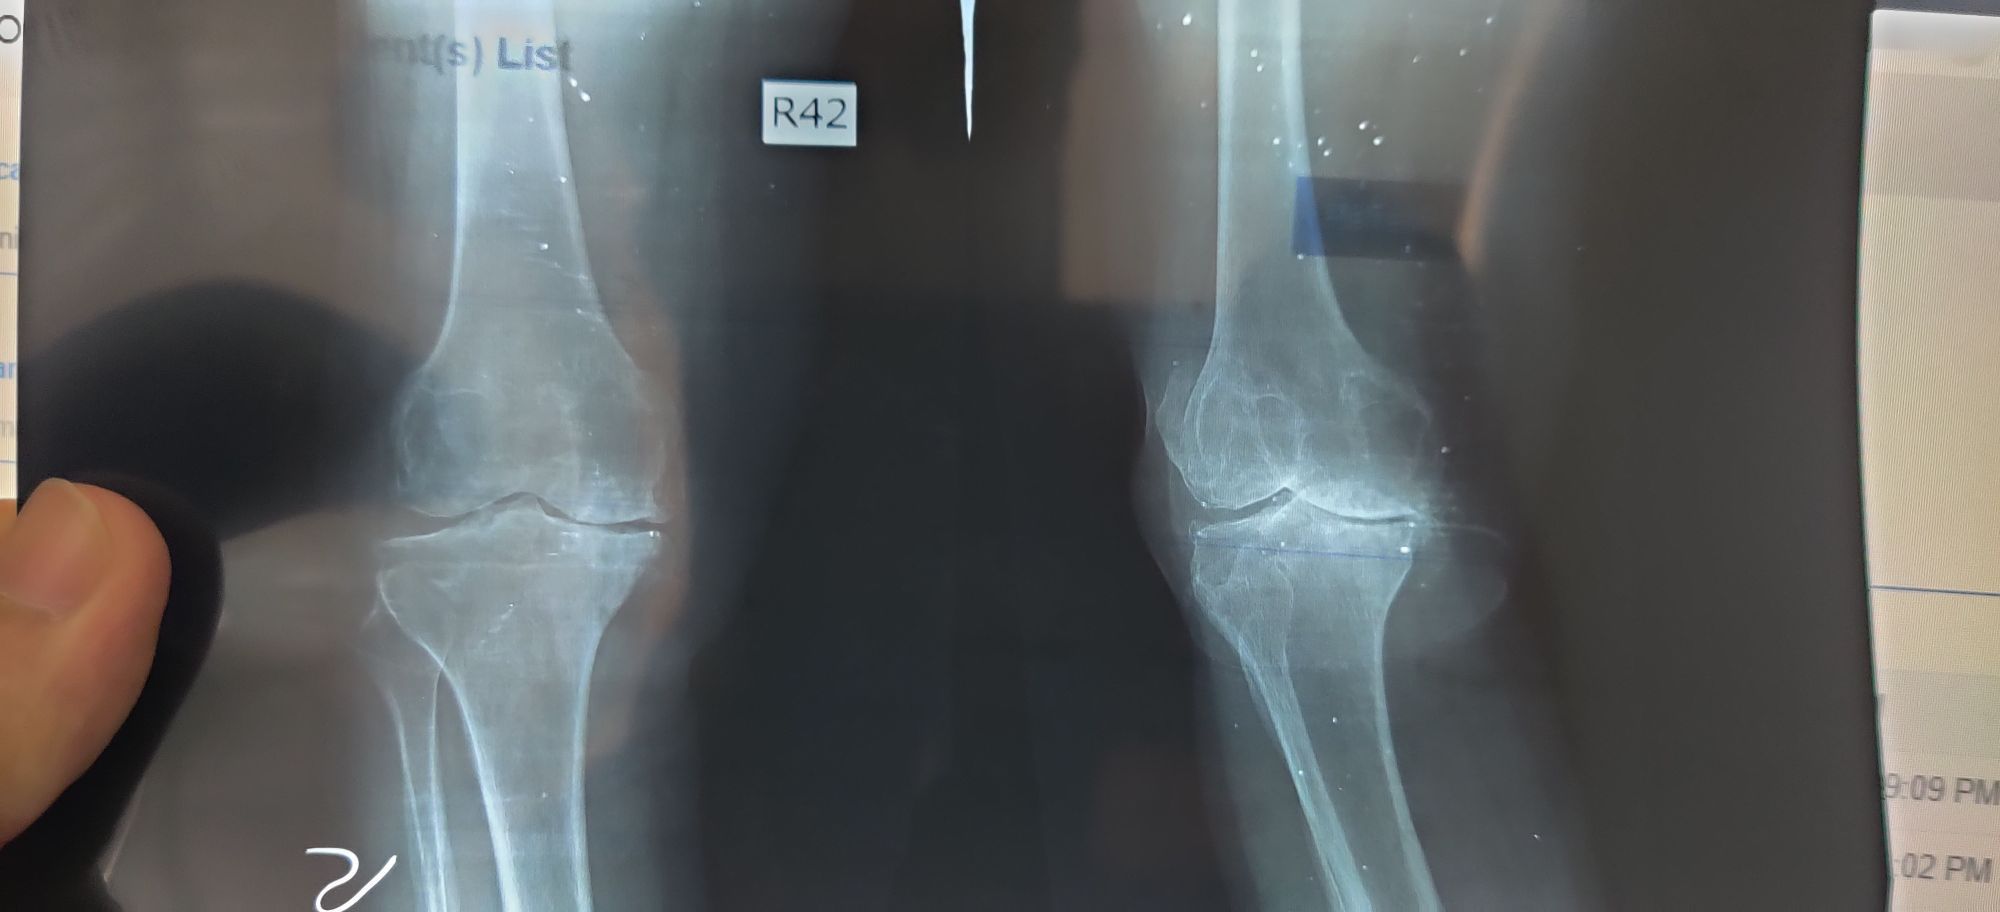

Osteoarthritis

Knee

Ortho

Oa